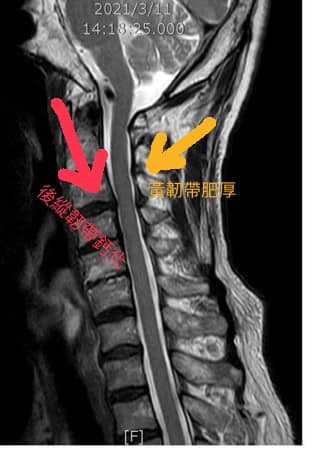

Cervical Spine Treatment Cases 精彩回顧 當醫生多年,第一次碰到這種的。 是哥太強!星星不夠給?🌟🌟🌟🌟🌟🌟 還是哥的針不夠... 2022.05.26 #感謝醫療奉獻獎得主簡志成醫師熱情見證 #超級熱血牙醫偏鄉童的一句讓他心臟裝7支架還... 2022.05.25 面對患者必須全力以赴💪💪💪💪💪 又是一個脊椎手術失敗嚴重沾黏案例😭 這些打釘子後的... 2022.05.20 功德迴向給十萬哥!祝福他。 2022.05.18 各位針友,要怎麼處理?? 強大律師團要出動了嗎?? 2022.05.18 患者的回饋太有梗了。 脊椎整合中醫微創療法逆轉勝。 原本醫學中心神外都說一定要開刀... 2022.06.04 夜訪「送子觀音」不孕症權威。 2022.06.05 行醫快十年,第一次收到特別的禮物。 2022.05.11 🔘感謝台灣股王某科技業副總經理,超生動活潑的五星評論,我差點感動到哭了,還有藏頭... 2022.05.10 頸椎神經根病變患者,寫的特殊的回饋。 居然直接素描我的樣子!!留下評論 💪💪💪屌針... 2022.04.09 想到當年推廣超微針刀的照片 2022.04.13 我想說的是脊椎整合中醫微創雖然很屌!很厲害!救了很多人免於開大刀👍。 but,but,but... 2022.02.16 大安森林公園吃飽飯後閒晃,碰到中醫界扛 壩子!! 全聯會中醫師公會理事長,陳旺全醫... 2022.03.15 為了救他(椎間盤巨大突出患者),來診前已經無法趴跟躺,只能用很怪異角度斜躺在治療... 2022.02.12 這不是葉佩雯😂。 不是第一次也不是最後一次。 怕燙就不要進廚房。 常在河邊走那有不... 2022.01.27 ← 上一頁 2 3 4 5 6 下一頁 →